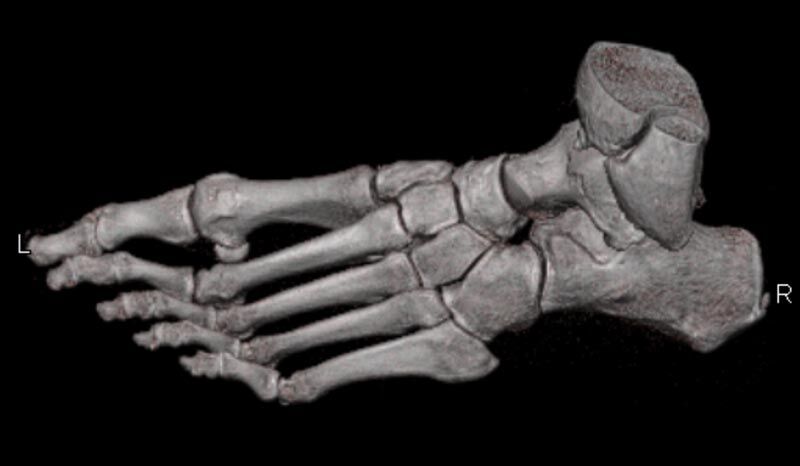

Extremitäten

• bei komplizierten Frakturen z. B. in der Nähe von Gelenken oder im Bereich der Handwurzel und Fußwurzel

• besonders hochauflösende, strahlendosissparende Darstellung aller Skelettstrukturen